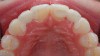

The few available adhesive systems of the 1970s and early 1980s were relatively hydrophobic in nature and unable to adequately penetrate the dentin smear layer, thus limiting their direct interaction with the tooth tissues. The smear layer is the residue that is left on the surface of the dentin after rotary instrumentation with diamond or carbide burs (Figure 1). It is a thin amorphous layer largely composed of degraded collagen, bacteria, and various inorganic dentin and enamel debris.6,7 Early adhesive systems were extremely limited and generally ineffective, in part because they bonded directly to the smear layer and were, thus, limited by the smear layer’s low intrinsic cohesive strength.8 Eventually, it was recognized that the smear layer needed to be removed and/or modified and bypassed in some fashion so that adhesive primers and resins could interact directly with the dentin. In the case of total-etch adhesive systems, the smear layer is essentially dissolved with phosphoric acid (H3PO4) and subsequently washed away during the rinsing step (Figure 2 and Figure 3). With self-etching systems, various acidic primers are used to modify, disrupt, and/or solubilize the smear layer and, although the remnants are not washed away as with total-etch systems, still permit direct adhesive interaction with the dentin substrate.9

Fig 1. Typical “peanut butter spread on toast” appearance of the dentin smear layer. (SEM courtesy of Jenny Wang.)

Figure 1